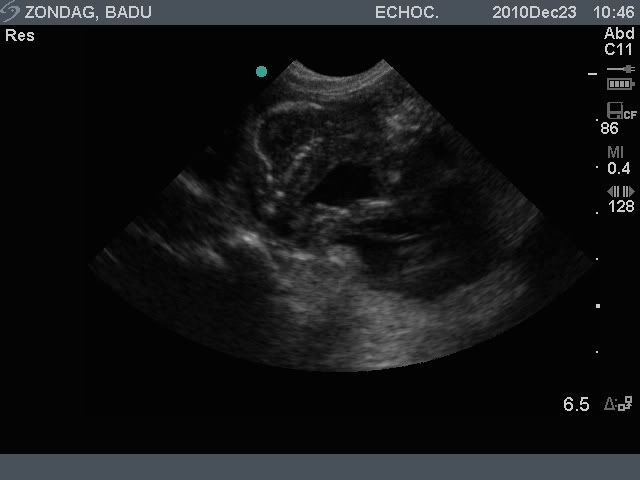

Vandaag zijn we voor een drachtecho geweest en…. we telden ongeveer 5 pups. Het aantal was niet helemaal goed te bepalen omdat mevrouw het een idioot plan vond om op haar rug te gaan liggen. Staand was het moeilijk tellen…